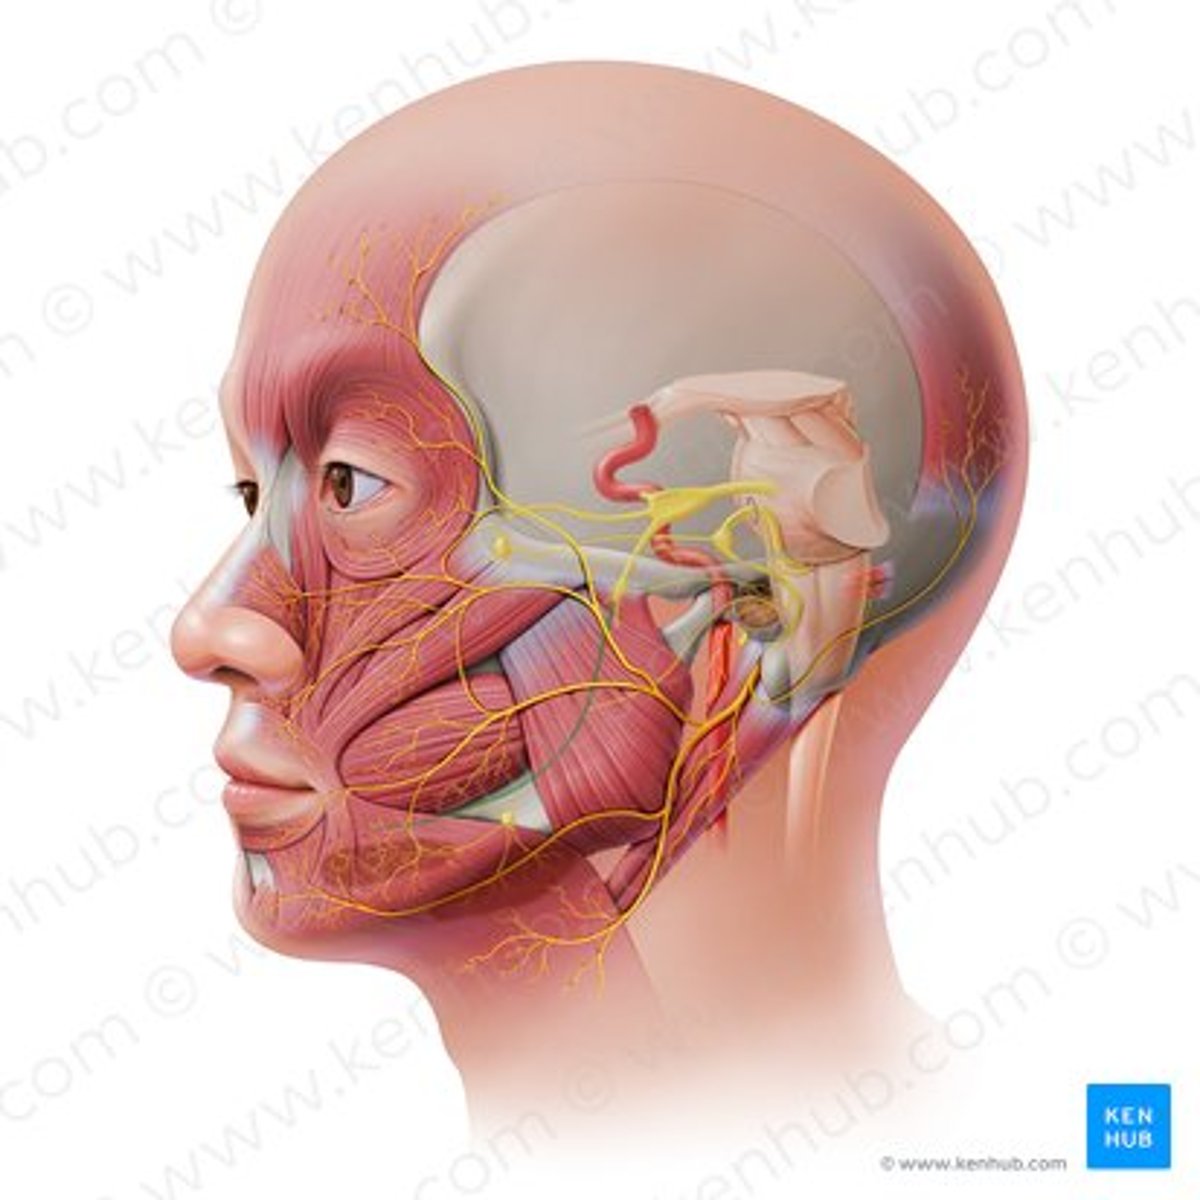

facial nerve (CN VII)